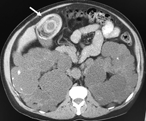

Massive retroperitoneal dedifferentiated liposarcoma in a young patient

Fernando X Moyon and others

Journal of Surgical Case Reports, Volume 2018, Issue 10, October 2018, rjy272, https://doi.org/10.1093/jscr/rjy272